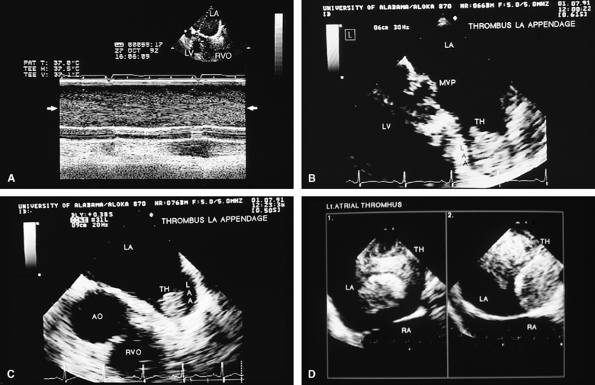

FIGURE 5.20. Porcine mitral prosthesis: spontaneous contrast and thrombus in the left atrium (LA). A. M-mode study shows spontaneous contrast (arrows). B,C. A large thrombus (TH) in the left atrial appendage (LAA). The prosthetic leaflets are only mildly thickened (B). D. Extensive thrombus formation (TH) in the left atrium in another patient with an obstructed porcine mitral prosthesis. AO, aorta; LV, left ventricle; MVP, mitral valve prosthesis; RA, right atrium; RVO, right ventricular outflow tract. (Creproduced with permission from Mahan EF III, Nanda NC. Transesophageal echocardiography. In: Rackley CE, ed. Challenges in Cardiology I. Mt. Kisco, NY: Futura, 1991:85–101. ) |